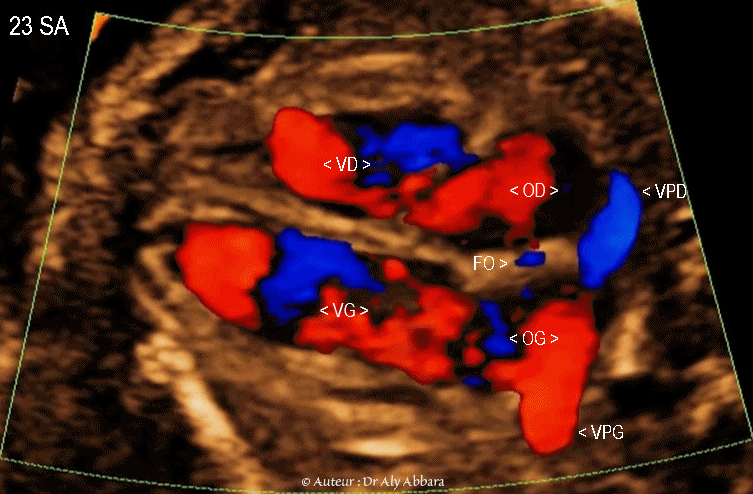

Images échographiques animées montrant à l'aide du Doppler-couleur le retour veineux vers l'oreillette gauche "OG" chez le fœtus ; il est composé :

I- Du retour veineux pulmonaire via les quatre veines pulmonaires (deux veines droites et deux veines gauches).

Sur ces images on identifie une veine pulmonaire gauche "VPG" et une pulmonaire droite "VPD"

II- Du flux sanguin veineux prévenant de l'oreillette droite "OD" via le foramen ovale "FO" ; une grande partie de ce flux sanguin provient du canal veineux (sang oxygéné) qui se jette dans la portion terminale de la veine cave inférieure, juste avant sa connexion à l'oreillette droite.

Ce shunt droit-gauche disparaît rapidement après la naissance par l’augmentation de la pression dans l'oreillette gauche (comparé à l'oreillette droite) qui aboutit à la fermeture du foramen ovale par la valvule de Vieusens.

Fœtus âgé de 23 SA